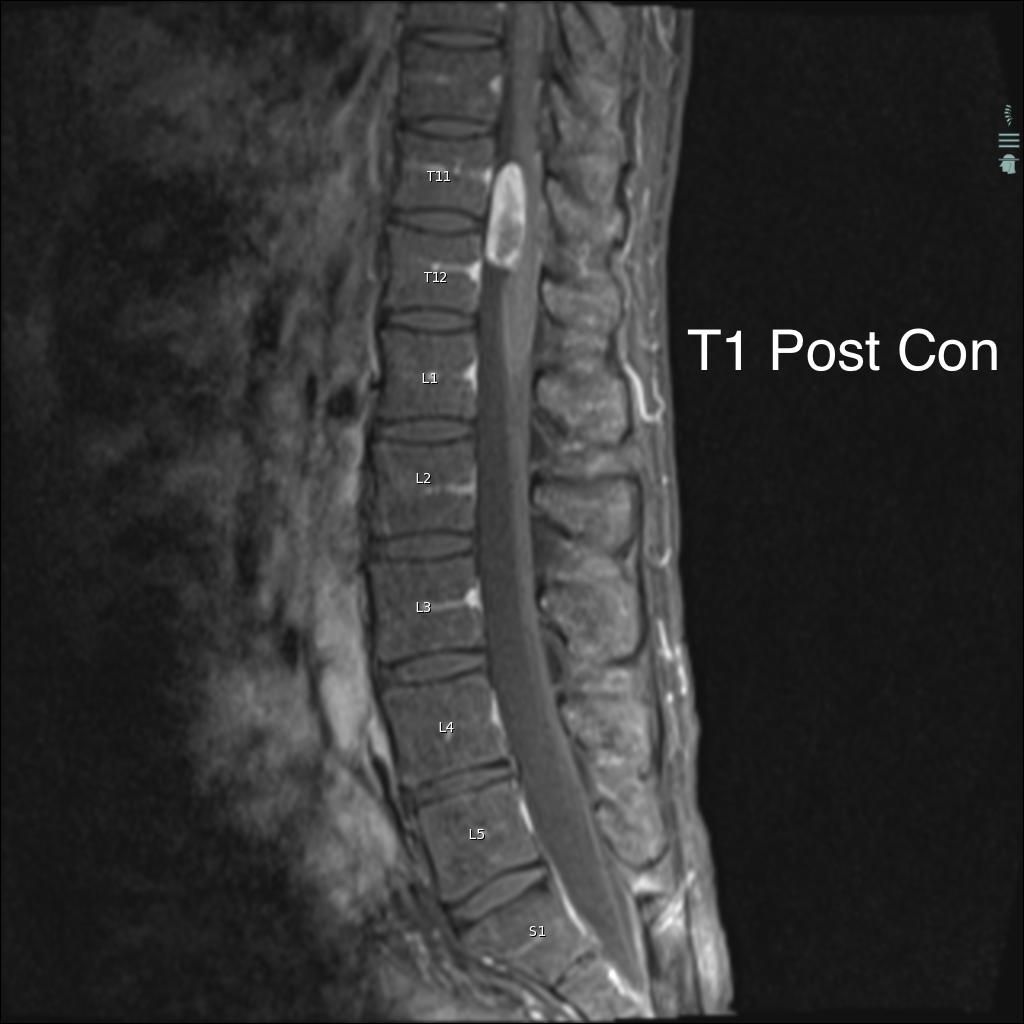

Can you diagnose this patient with low back pain, right lower extremity paraesthesias, and incontinence?

Case History: 40-year-old man with low back pain, right lower extremity paraesthesias, and incontinence. He presents 10 days later with worsening pain.

What is your diagnosis?